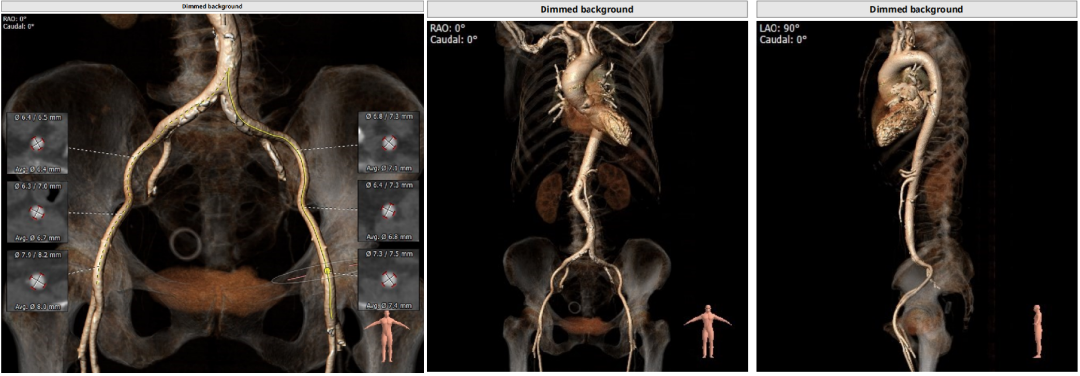

CT分析

以3个窦消失最低点确认的平面作为虚拟瓣环平面初步筛选瓣膜尺寸。自展瓣参考周长得出的Annulus直径,该病人为25.8,根据自膨胀瓣膜特点需要oversize,初步判断为29/32瓣膜。LVOT直径大于Annulus,短径24mm,足够限制瓣膜,提供锚定支撑力。STJ高度足够,可提供足够空间给原有瓣叶,过宽的STJ则无法提供释放中锚定支撑力。

窦部的空间与左右冠脉开口高度结合瓣叶形态,是否增厚可以初步判断瓣叶是否会在瓣膜植入后遮挡冠脉开口造成急性的冠脉堵塞。该病人左冠开口略低,且钙化集中在右冠和无冠窦,判断冠脉风险较高。需术中球扩判断是否进行冠脉保护。

升主动脉未见增宽,心脏角度合适极重度钙化,多集中在基底部位二叶瓣重度钙化THV需要downsize选择26/29瓣膜。

Anulus 27,LVOT 34.2,短径25.9,STJ高度可,初步预估32/29瓣膜。

窦部短径26mm、左右冠空间足够,冠脉高度可心脏角度51°、升主未增宽。

Annulus:23.5,初选26/29瓣膜。LVOT短径19.3mm,STJ高度足够,宽度适中。

窦部空间足够,升主增宽,左右冠高度合适。

Anulus 25.7、LVOT 23.7;STJ高度可,窦部空间足够;初步预估29/32瓣膜。

升主未见增宽,角度尚可,轻度钙化。

左右冠高度不低,球扩体位:LAO 26、CRA 18;释放体位:LAO 9、CRA 4;心室腔略小。

入路直径足够,分叉点足够高。右股作为主入路。